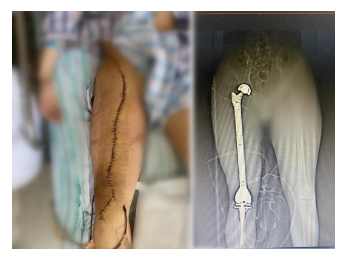

【技术·瘤】全股骨置换术让花季少年免受截肢之痛

手术正式开始。与前期预判一致,肿瘤周围滋养血管异常丰富,密密麻麻的包裹了整个瘤体。但在赵军主任、杨蕴主任、吴海啸医生和杨松巍医生的通力合作,仅用两个小时就切除了被肿瘤包裹的整个右侧股骨,并保留了患肢的股动静脉和坐骨神经,为重建肢体带来了希望。随后,手术团队对胫骨近端进行精确截骨,重建了膝关节和髋关节,恢复了患者的肢体功能。

经过科室医护人员的悉心治疗,目前,患者已顺利度过了术后危险期,伤口一期愈合,没有感染等并发症,已经可以在支具的保护下站立。后期还将为患者进行进一步辅助化疗。